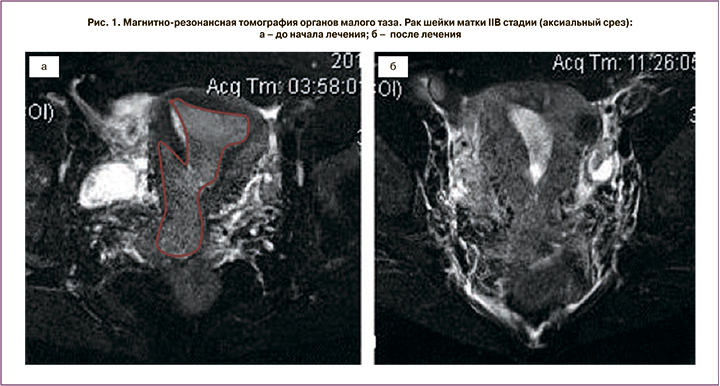

Пациентка Д., 43 лет, обратилась с жалобами на боли внизу живота, кровянистые выделения из половых путей различной интенсивности. При обследовании установлен диагноз РШМ IIB стадии. Биопсия подтвердила плоскоклеточный гистотип опухоли. По данным МРТ малого таза опухоль максимальным размером 67 мм распространялась на тело матки и инвазировала клетчатку параметрия справа. Была выполнена двусторонняя ХЭ маточных сосудов лекарственно-насыщаемыми микросферами Hepaspheres. В качестве цитостатика использовали препарат оксалиплатин в дозировке 100 мг.

Через 3 недели после операции выполнена МРТ малого таза с контрастированием. Эффект от лечения расценен как частичный ответ (рис. 1, 2), что позволило провести хирургическое лечение в объеме операции Вертгейма, после чего пациентка получила адъювантный курс лучевой терапии. По настоящее время рецидива не зарегистрировано, время наблюдения составило 26 месяцев.